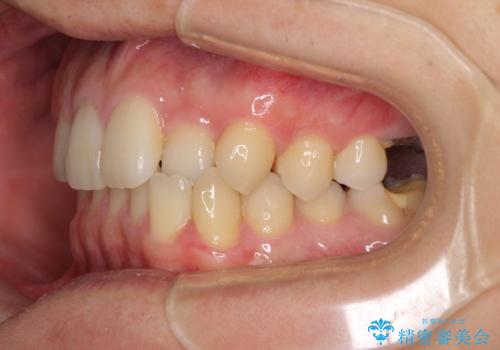

前歯のクロスバイトと抜歯が必要な奥歯の虫歯 インビザラインとインプラント治療

- 前歯のクロスバイトと、大学生のころから放置している虫歯を気にして来院された患者様です。

マウスピースでの矯正治療を希望されていましたが、前歯のクロスバイトは不十分な仕上がりや歯髄壊死などのリスクが高くなるため、術前にワイヤーで大まかに整えてからインビザラインにて矯正治療を行うこととしました。

奥歯の虫歯は抜歯が必要であったので、矯正治療前に抜歯をし、矯正治療と並行してインプラントによる補綴治療を行うこととしました。